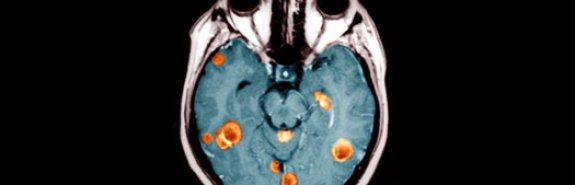

Ученые из Колумбийского университета обнаружили два гена, ответственные за возникновение одной из наиболее быстро развивающихся форм рака головного мозга

Так называемая Glioblastoma multiforme в считанные месяцы приводит к развитию неоперабельной опухоли, однако до сегодняшнего дня медики не могли понять причину столь стремительного протекания заболевания.

Как сообщает cybersecurity.ru, исследование группы ученых указывает в качестве наиболее возможной причины пару генов: C/EPB и Stat3. Оба гена работают вместе, "запуская" генетическую цепочку, приводящую к превращению здоровых клеток мозга в раковые.